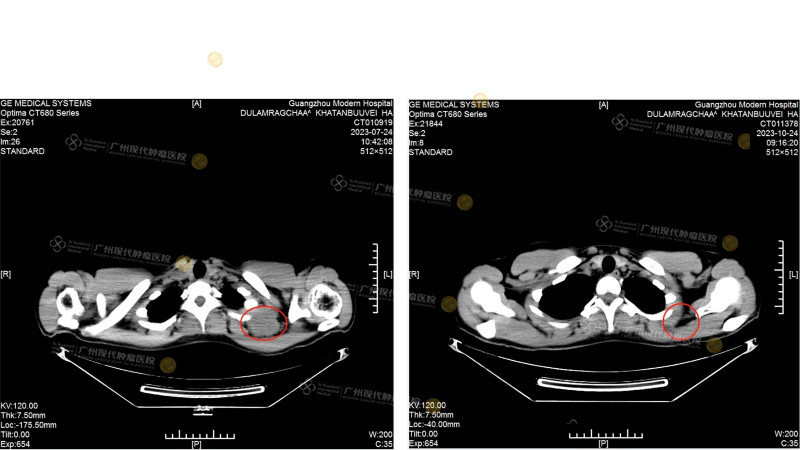

[ภาพด้านซ้ายคือ CT scan ของกระดูกสะบักในเดือนกรกฎาคม: ขนาดของก้อนเนื้อประมาณ 46 มม.×79 มม. และลุกลามเข้าไปในกระดูกสะบัก]กับ[ภาพด้านขวาคือ CT scan ของกระดูกสะบักในเดือนตุลาคม ก้อนเนื้อหายไป]

[ภาพด้านซ้ายคือ CT scan ของต่อมน้ำเหลืองที่คอในเดือนกรกฎาคม: ก้อนเนื้อมีเส้นผ่านศูนย์กลางประมาณ 50 มม.]กับ[ภาพขวา CT ต่อมน้ำเหลืองที่คอในเดือนตุลาคม ก้อนเนื้อหายไป]